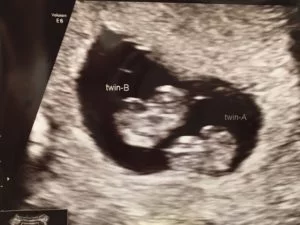

It wasn’t until I was 8 weeks and 5 days pregnant that I found out I was pregnant with identical twins!!

Luckily my husband had come with me to the early ultrasound and my mother-in-law was caring for our 1-year-old. I remember the ultrasound technician said “Oh, there’s two” but nothing further.

My husband and I thought, two what?! Two arms? Two legs? What? Though honestly I don’t know what we actually said.

We must have asked something like that, to which she replied, “There are two babies.”

My husband about fell out of his chair and thankfully I was laying down so I wasn’t going anywhere. Twins. A total shock.

First we wanted to know what type of twins we were having, identical twins or fraternal twins. Answer = MoDi identical twins who have a shared placenta but have their own amniotic sacs. We didn’t even know that was a thing!